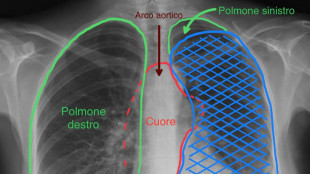

Grande tumore asportato alle Molinette sollevando il cuore

La massa di venti centimetri al timo comprimeva anche un polmone